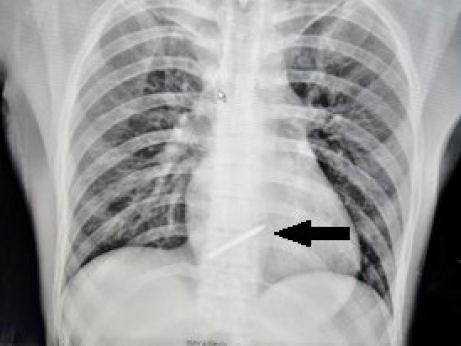

图1:胸片显示体内的钉子

患者,25岁,男性。在进行装修作业时意外将钢钉射入体内被紧急送往急诊科治疗。临床检查,患者意识清醒,血压80/50mmHg,心率120 次/分,胸部左侧锁骨中线第二肋间有一个约2cm大小的开放性创伤。胸部X线显示一颗钉子与心影重叠。经胸超声心动图显示约1cm心包积液。胸部CT显示钉子处于胸骨后且钉子头部指向右心室,患者被紧急送往手术室。术中发现钉子头部已经穿透心包表面,未伤及心脏,医生顺利将其取出,术后患者病情平稳,7天后顺利出院。